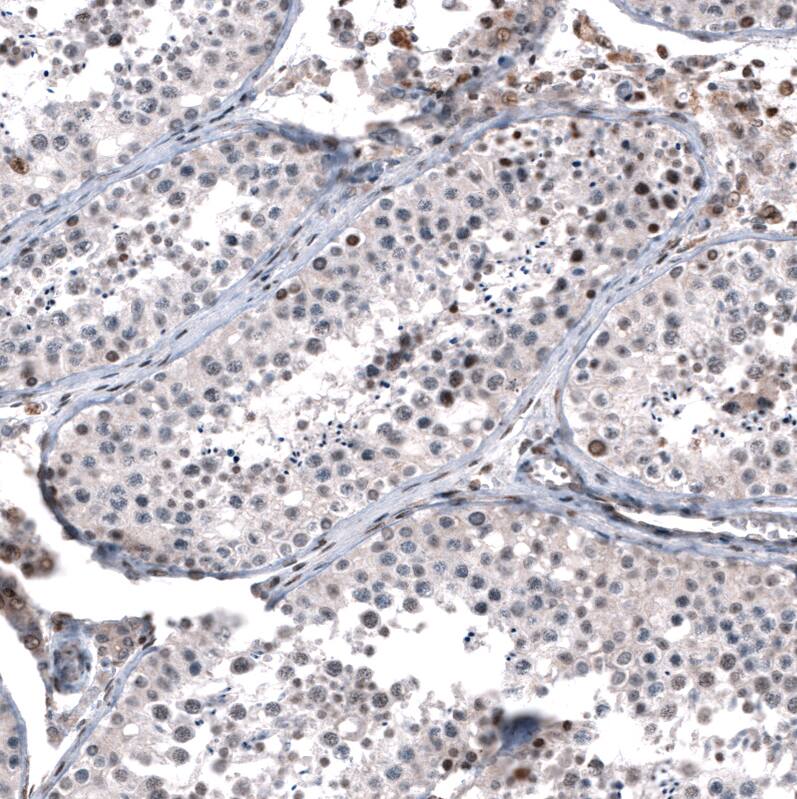

Staining of human testis shows moderate to strong nuclear positivity in a subset of cells in seminiferous ducts.